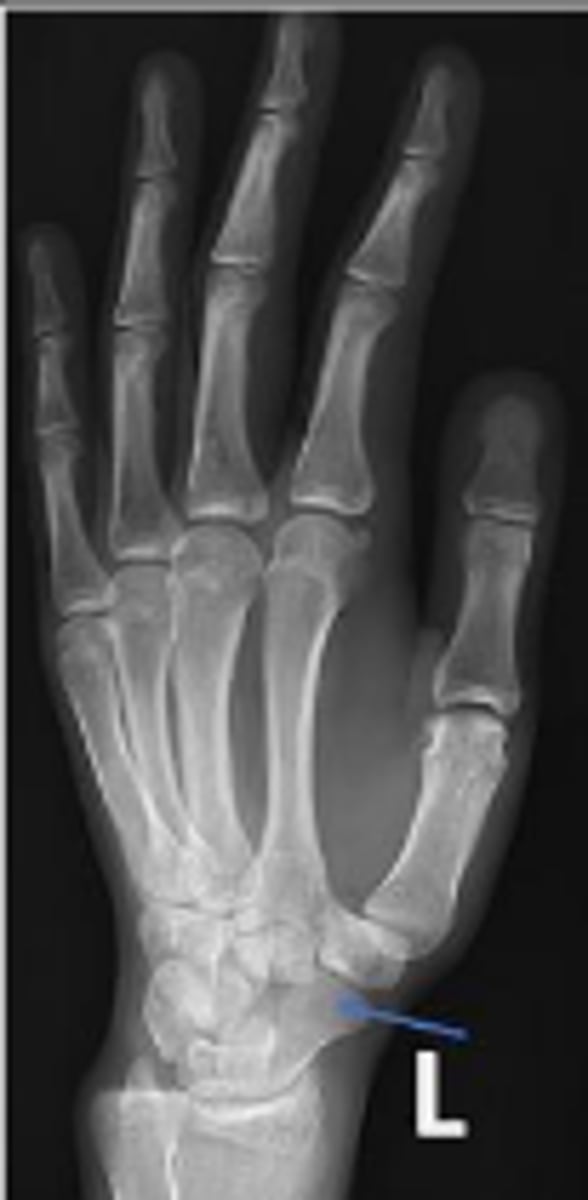

PA of the left wrist

What is the name of the radiographic view?

Left scaphoid

What is outlined?

Left pisiform

What is the arrow pointing to?

Left capitate

Volar margin of the left radius

Dorsal margin of the left ulna